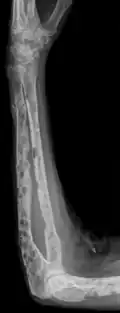

-

X-ray of the forearm, with lytic lesions -